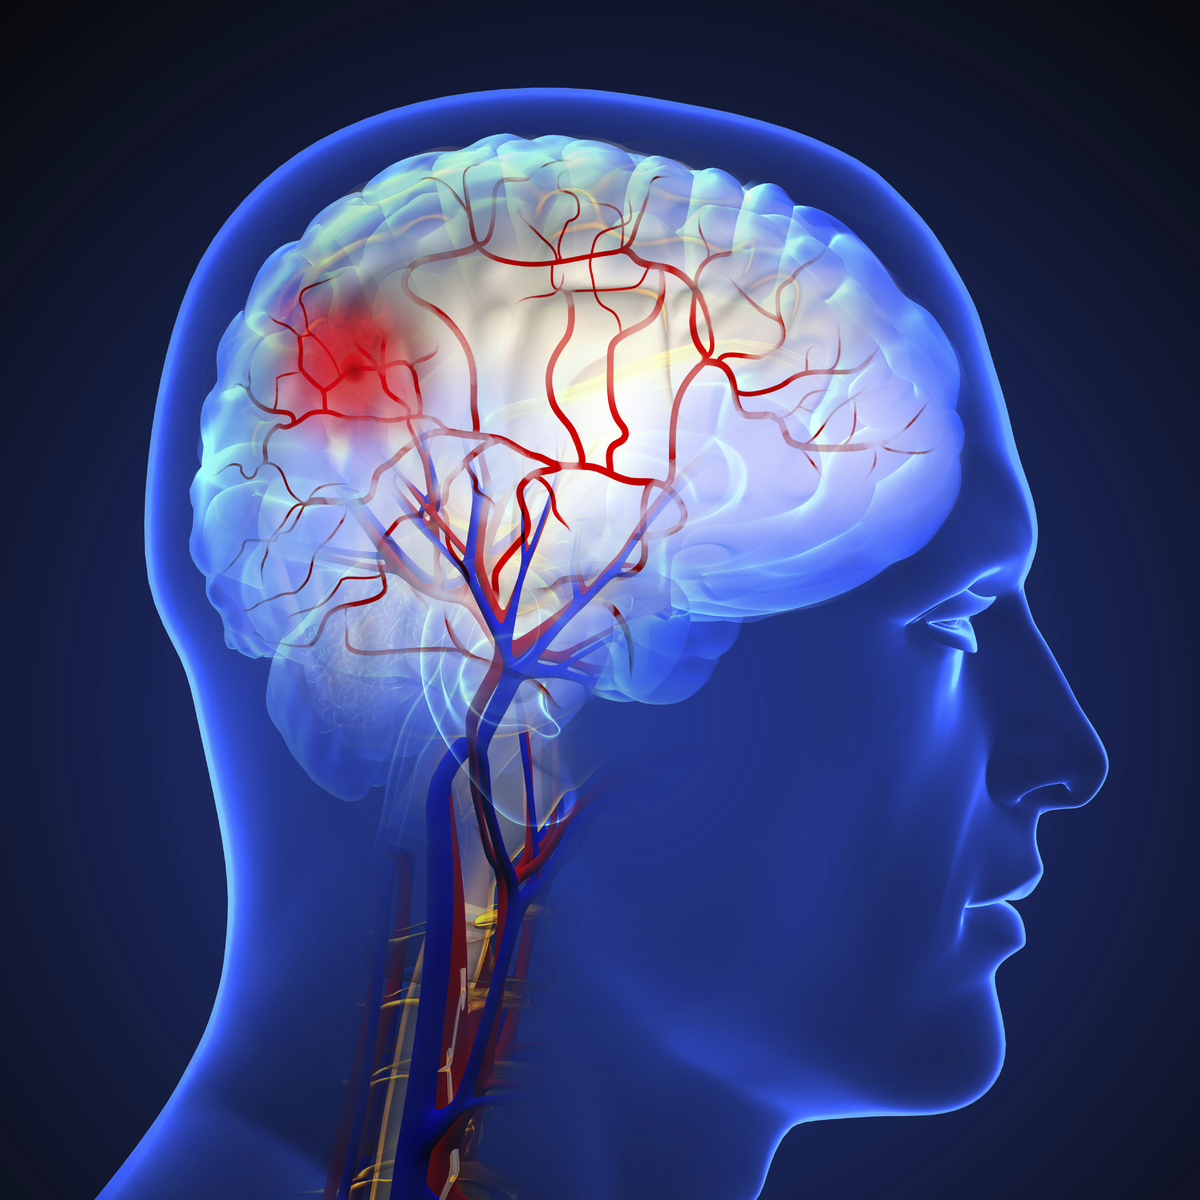

기온이 급격히 떨어지는 겨울철에는 혈관이 수축하고 혈압이 오르면서 뇌졸중 위험이 커진다. 전문가들은 불필요한 실외 활동을 줄이고 방한용품으로 체온을 유지하는 등 예방 수칙을 지킬 것을 당부한다.

뇌졸중은 뇌혈관이 막히는 뇌경색(허혈성)과 혈관이 터지는 뇌출혈(출혈성)로 나뉜다. 질환 특성상 24시간 대응이 필요하고 중환 비율이 높아 치료 과정의 위험도 크다.

건강보험심사평가원에 따르면 뇌졸중 환자는 ▲2018년 59만 1946명 ▲2019년 61만 776명 ▲2020년 60만 2161명 ▲2021년 62만 504명 ▲2022년 63만 4177명으로 증가 추세다. 2022년 기준 진료 환자는 70대(19만 5608명), 60대(17만 4109명), 80세 이상(16만 6978명) 순으로, 고령층에서 각별한 주의가 요구된다.

증상은 손상 부위에 따라 다양하지만, 대부분 신체 한쪽에서 나타난다는 점이 특징이다. 전신 위약감이나 양쪽 팔다리 감각 저하는 다른 원인일 가능성이 크다. 전조증상 확인에는 Face·Arm·Speech·Time의 ‘F·A·S·T 법칙’이 유용하다.

웃을 때 한쪽 얼굴이 처지거나 한쪽 팔에 힘이 빠지거나 말이 어눌해지면 즉시 119에 신고해 병원을 찾아야 한다.

이대서울병원 신경과 박무석(사진) 교수는 “뇌졸중은 증상이 갑작스럽게 나타나 치료 시기를 놓치면 심각한 후유증이나 사망으로 이어질 수 있다”며 “증상 발생 직후 골든타임 4시간 30분 이내 병원을 찾아 신속한 진단과 치료를 받아야 한다”고 강조했다.

박 교수는 “갑작스러운 심한 두통, 어지럼증, 시야 장애도 전조 신호일 수 있다”며 “일시적 증상이라도 가볍게 넘기지 말아야 한다”고 말했다. 이어 “고혈압·당뇨·고지혈증 관리, 절주와 금연, 규칙적인 운동은 첫 발생뿐 아니라 재발 예방에도 도움이 된다”고 덧붙였다.